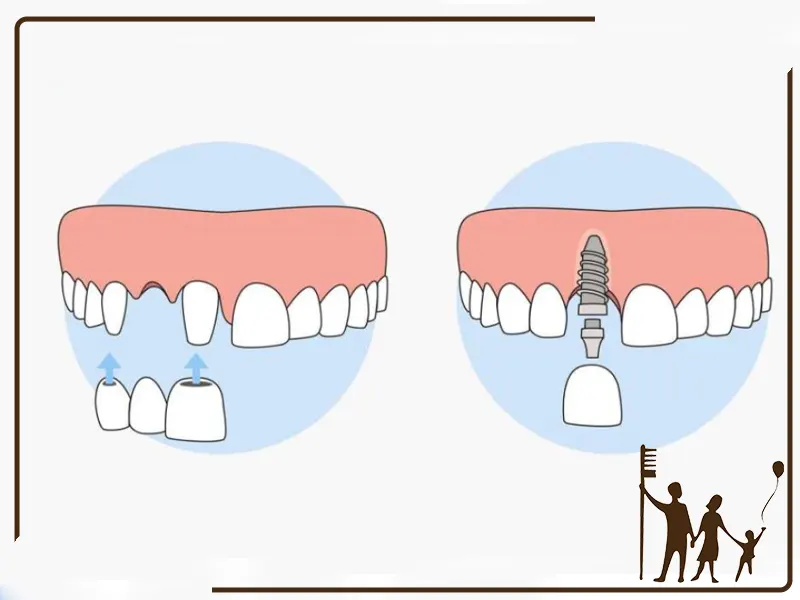

ایمپلنت تکدندان: راهحلی برای جایگزینی یک دندان از دست رفته

ایمپلنت تکدندان، یک پایه تیتانیومی است که در استخوان فک قرار میگیرد و تاج دندان مصنوعی روی آن نصب میشود. این روش، جایگزینی دائمی و طبیعی برای دندان از دست رفته ارائه میدهد.

ایمپلنت چنددندان: راهحلی جامع برای جایگزینی چندین دندان از دست رفته

ایمپلنت چنددندان، شامل قرار دادن چندین ایمپلنت در فک است که میتوانند از بریج یا دندان مصنوعی پشتیبانی کنند.

۲. تعداد پایه ایمپلنت

تک دندان: به ازای هر دندان، یک پایه ایمپلنت لازم است.

چند دندان: یک یا چند پایه ایمپلنت برای پشتیبانی چند تاج استفاده میشود و بسته به طراحی پل، تعداد پایهها کمتر از تعداد دندانهاست.